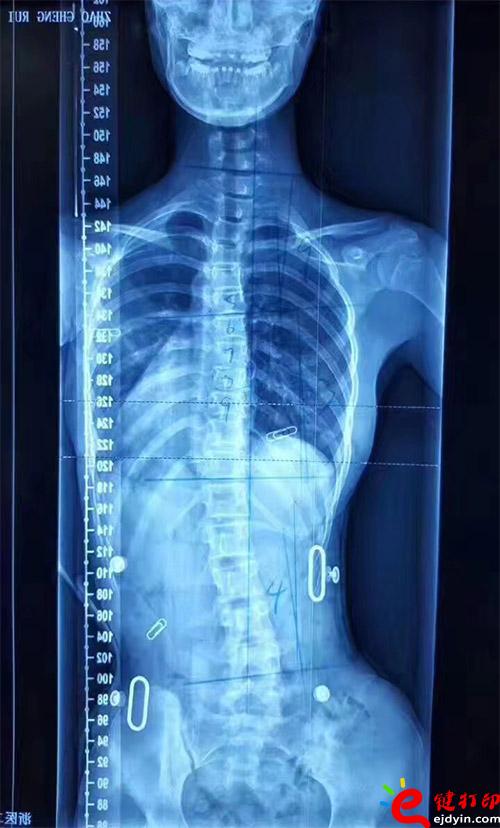

3D打印矯形器

不多說,直接上案例就知道了。這是真實案例。

在脊柱側彎患者中,僅有10%的青少年特發性脊柱側彎患者最終需要手術治療,90%的患者可以保守治療和積極觀察。非手術治療中公認最主要和可靠的方式是用矯形支具治療。像上圖這樣的案例就可以通過矯形器治療。每個人的畸形不一樣,就需要像3D打印這樣可定制又便宜的技術幫助。